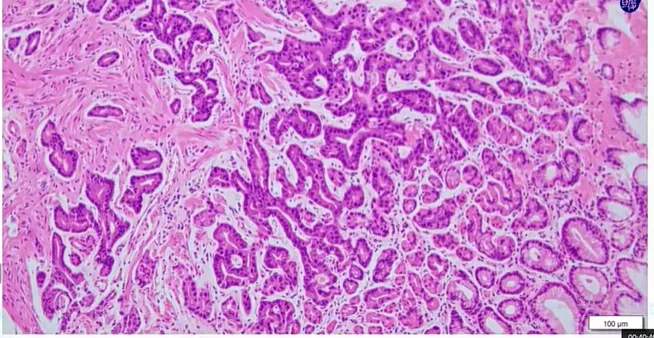

【“胃底腺型腺癌 / 泌酸腺腺瘤”的镜下特征】:结构异型+两种细胞特征

• 分化程度分化极好,形态接近正常胃底腺细胞;以主细胞为主型,壁细胞多分布于肿瘤边缘 / 表面。

• 异型性细胞异型性极低,仅见胞增大、密度增高,可复层 / 多层排列;核从基底层上移,核分裂像罕见。

• 增殖活性Ki-67 阳性率多小于 5%。

组织结构

• 腺体结构复杂,相互吻合形成 “endless glands”(无尽腺体);少见筛状结构,无坏死

主要由主细胞分化细胞构成,细胞呈柱状,胞质偏嗜碱性,腺体具有明显结构异型,包括不规则分支、扭曲等,与周围正常胃底腺明显不同。低级别胃底腺型肿瘤包括OGA和GA-FG,二者具有相同的临床及病理特征,鉴别点为是否伴有黏膜下浸润。OGA为具有胃底腺分化的位于黏膜内的上皮性肿瘤。GA-FG为具有胃底腺分化的低异型性分化型腺癌,伴有黏膜下浸润。